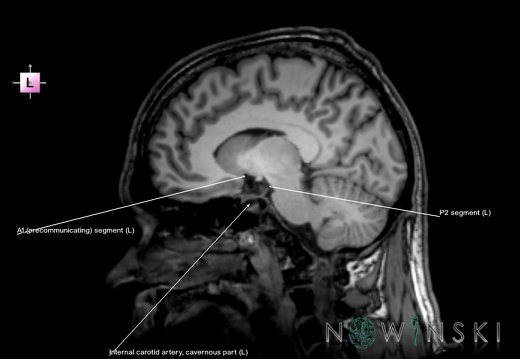

G6.T15.2.V2.P30.Intracranial arteries–Triplanar

G6.T15.2.V2.P30S.Intracranial arteries–Triplanar